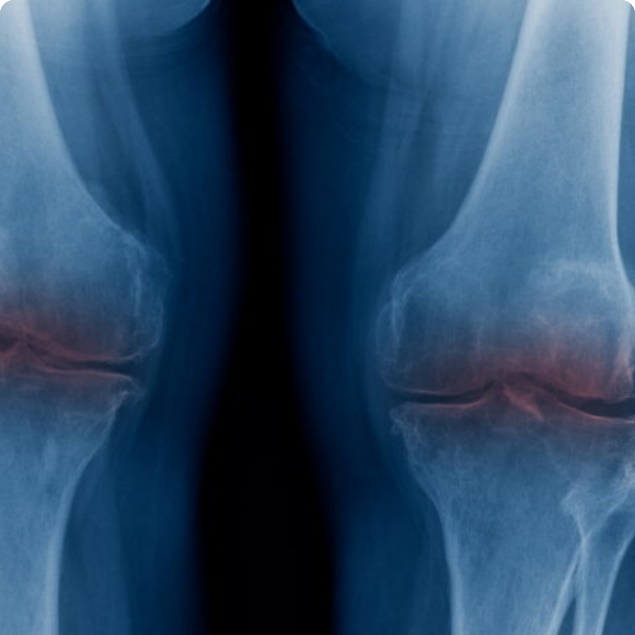

KNEE REPLACEMENT SURGERY

KNEE REPLACEMENT SURGERY

Knee replacement surgery is a highly effective procedure to relieve pain and restore function in patients with severe knee arthritis or damage, offering long-term improvements in mobility and quality of life.